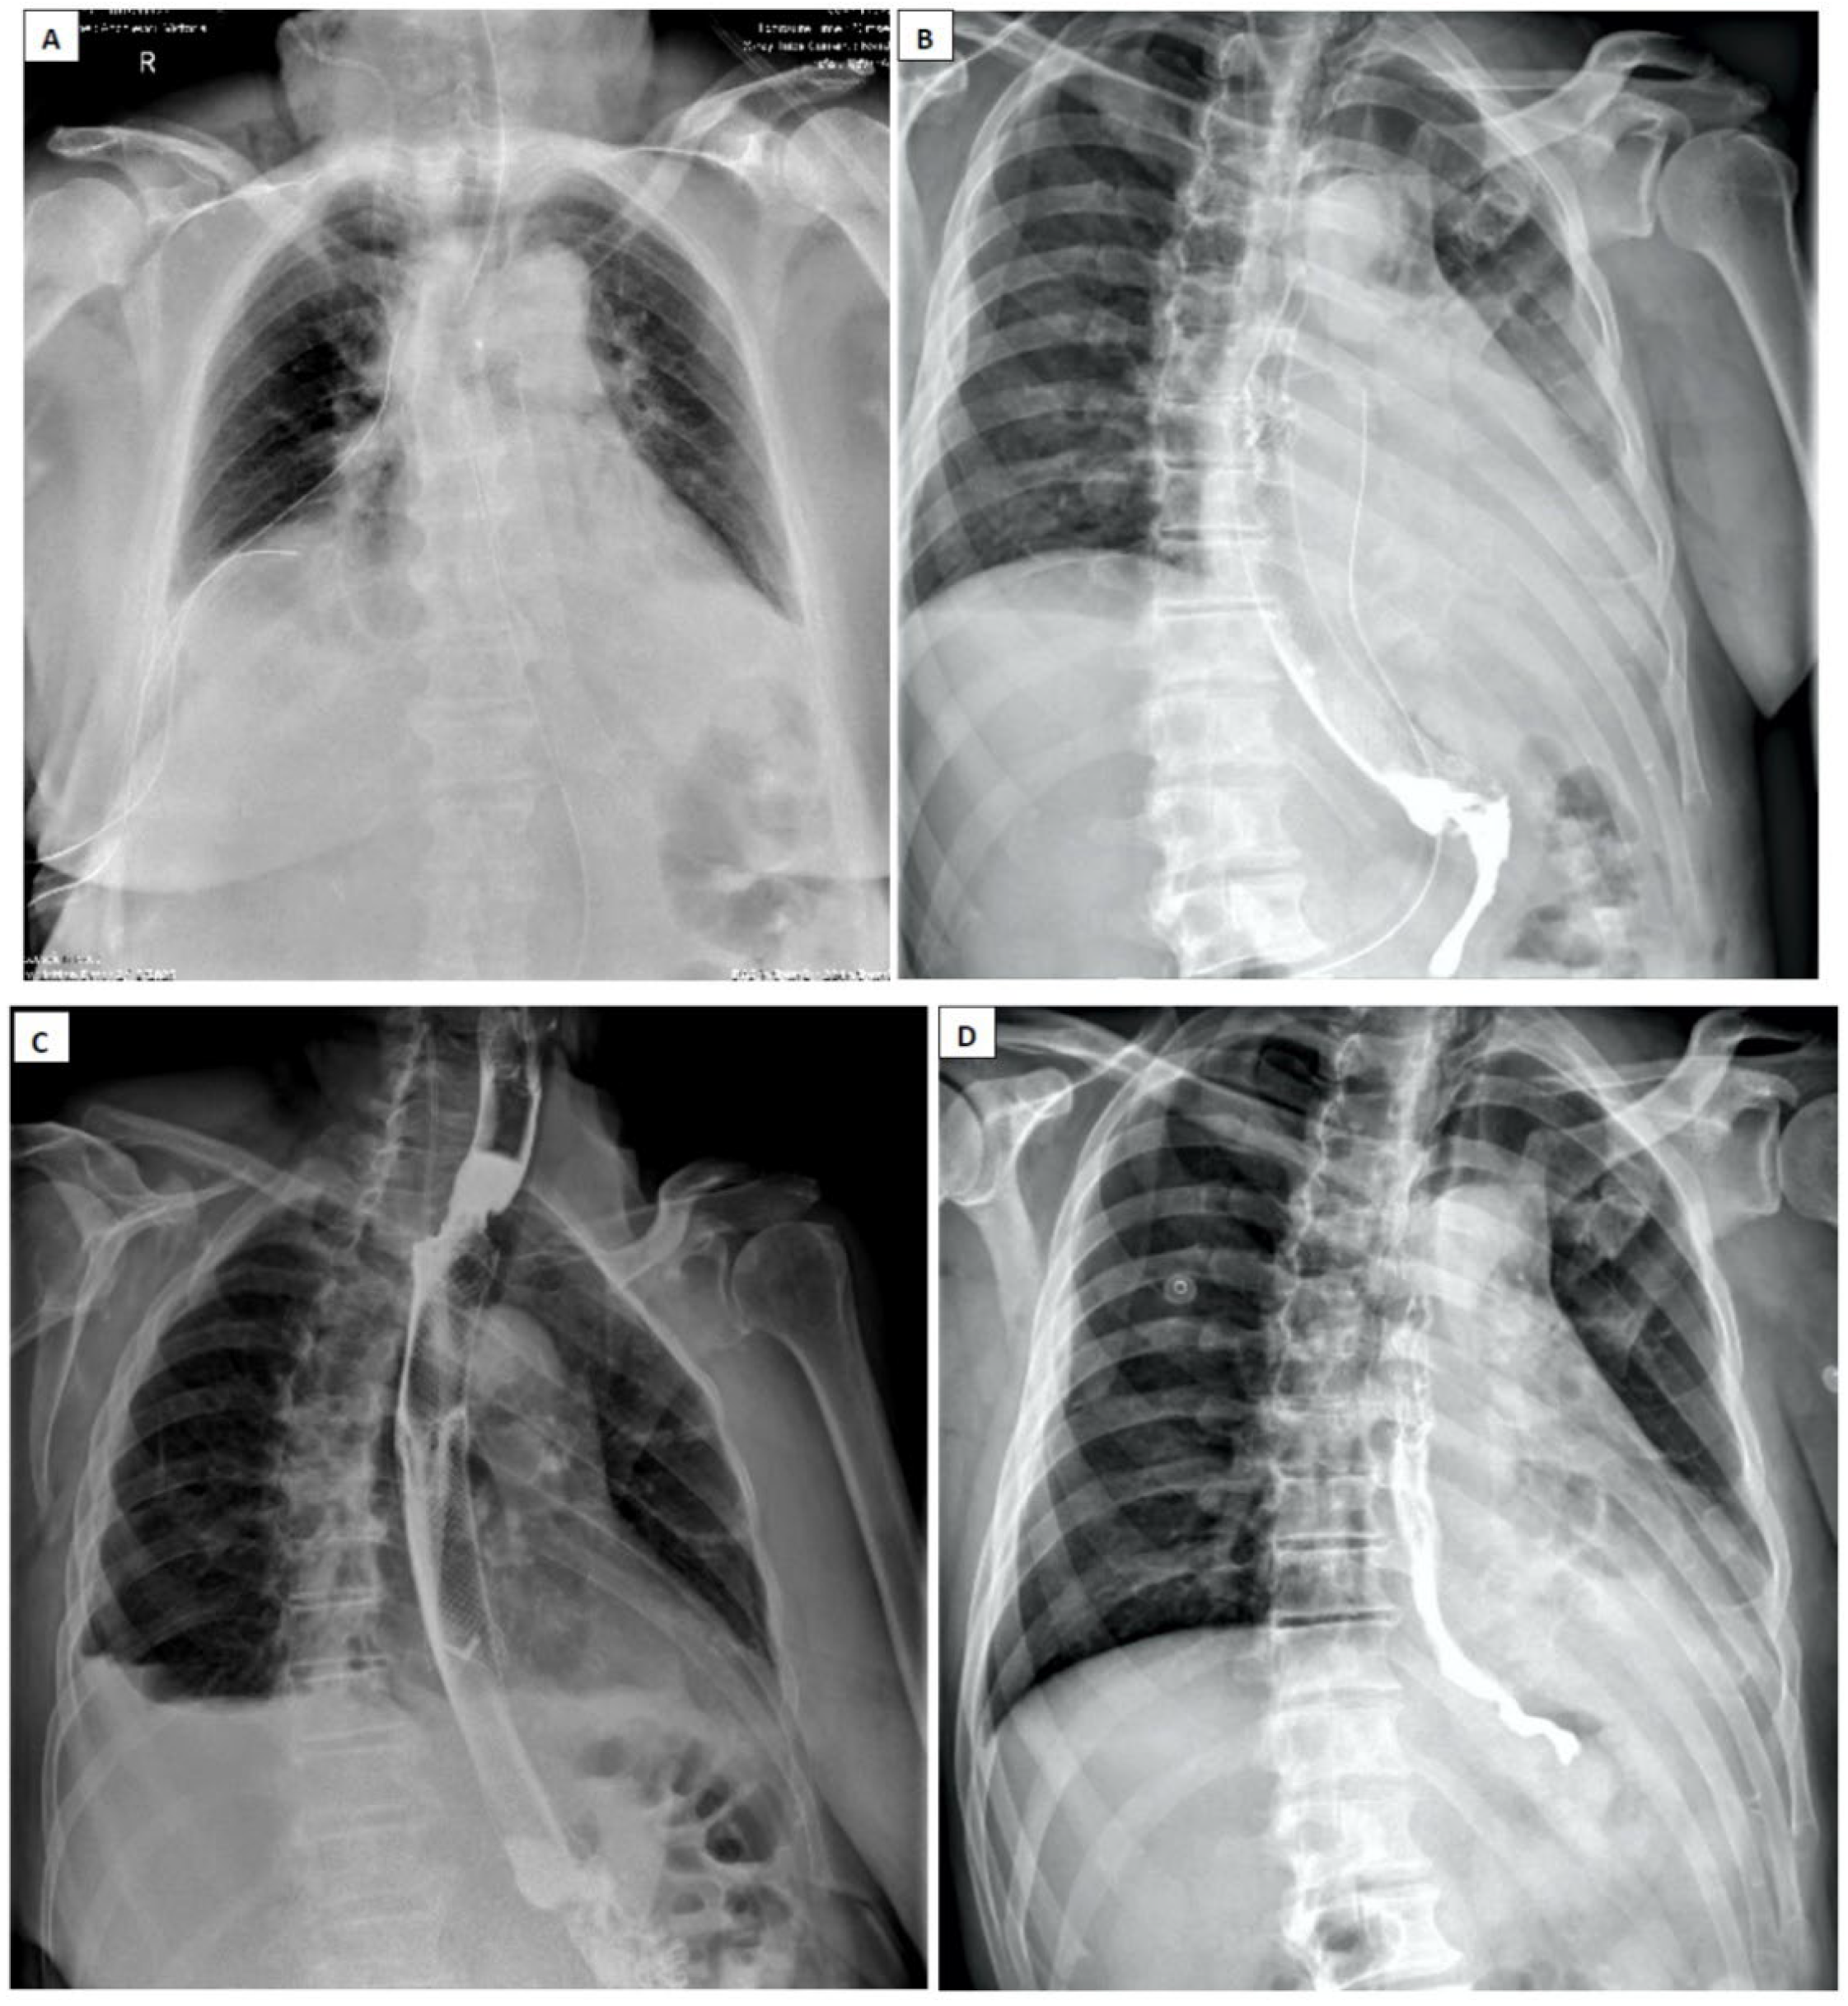

- Pneumomediastinum

- Pneumothorax (especially left-sided)

- Pleural effusion (especially left-sided)

- Pneumoperitoneum